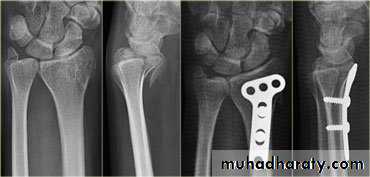

Smith fracture :

Treatment :

Volar or dorsal sublaxation,Treatment : undisplaced fracture: casting below elbow for 6wks.

Displaced fracture: open reduction and internal fixation.